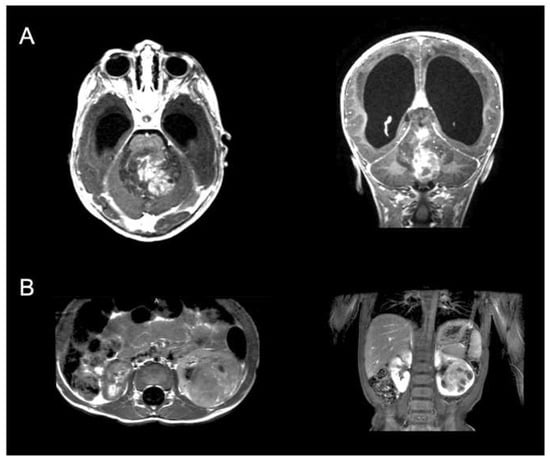

Although rare, one underexplored presentation is pediatric CNS tumors within the brain that present with metastasis away from the primary site, including the brain, bone, and solid organs such as the liver and kidney (Figure 1). What makes this particular cohort special is that the definition of metastasis in the setting of a primary brain tumor can include other distinct sites in the brain and spine, as well as other sites outside the CNS, which is more typical by definition [4,5]. Institutional series estimate that these metastases of pediatric CNS tumors will occur in approximately 0.5–2% of all presenting pediatric brain tumors, although more pathology-specific series indicate this could be as high as 40% [6,7,8,9].

Figure 1. Example of a 15-month-old boy that presented with a 5-month history of spasticity in lowers, headaches, and vomiting. (A). MRI of the brain revealed a large fourth ventricular mass with associated hydrocephalus, and (B). MRI of the abdomen demonstrated left renal mass. Ultimately, the patient was taken to the operating room for decompression of the fourth ventricular mass without issue, and then, four weeks later, underwent a partial left nephrectomy. Pathology of the brain lesion revealed a diagnosis of Atypical Teratoid/Rhabdoid Tumor (ATRT) and similar histology for the renal lesion, indicating metastatic disease. The patient subsequently underwent adjuvant radiation therapy and chemotherapy. Two years later, the patient remains alive, having undergone two CSF diversion procedures, and continues to receive adjuvant treatment.